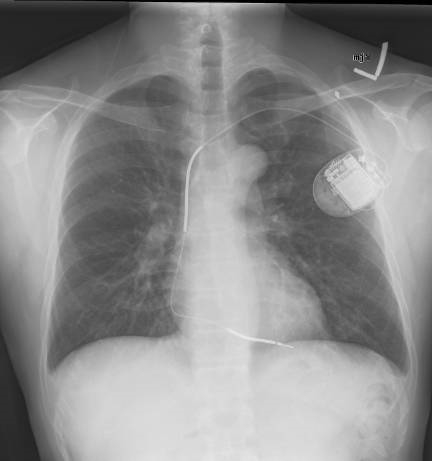

CXR for the case found here:

(CXR source:

https://commons.wikimedia.org/wiki/File:Implantable_cardioverter_defibrillator_chest_X-ray.jpg)